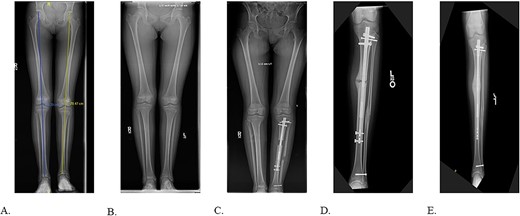

The patient was positioned supine on a radiolucent table with fluoroscopy coming from the contralateral side. The prior infrapatellar scar was incised, revealing bony ingrowth around the proximal end of the implant. A 3.2-mm guide pin was advanced into the center of the implant and a cannulated reamer removed the bony overgrowth. Residual bone surrounding the proximal implant was debrided using a bone curette and then a Nuvasive© conical extractor was attached to the exposed receiving end. The remaining proximal interlocking screw was localized under fluoroscopy and removed. When backslapping the implant, the components disassociated, and the telescopic portion remained lodged in the tibial medullary canal. When consulted intraoperatively, the mother chose to remove all implants by means of tibial osteotomy. An 8 cm long anterior ¼ circumference of the tibia unroofing osteotomy was performed using multiple drill holes and osteotomes (Fig. 2A/B). The remaining portion of the implant was removed with a clamped vice grip and mallet. (Fig. 3A/B). The osteotomy was reduced using a point-to-point reduction clamp and secured with three 2.7-mm lag by technique screws. The wound was irrigated, and 5 cc of demineralized bone matrix was applied to bolster osseous healing.

Final radiographs showed adequate alignment, internal fixation of the tibial osteotomy, and complete hardware removal aside from the three new fixation screws (Fig. 4A). The incisions were closed, dressed and the leg was immobilized in a Controlled Ankle Motion (CAM) boot. The patient spent six weeks non-weight bearing but was able to return to work without any pain or limping at three months post implant removal (Fig. 4B). Final 12-months follow-up demonstrated radiographically healed osteotomy site and maintained equal limb lengths and alignment (Fig. 5A-C).

A: Intraoperative radiograph demonstrating complete implant removal with x3 fixation screws. B: 6 weeks postoperative radiographs demonstrating maintained alignment at osteotomy site.